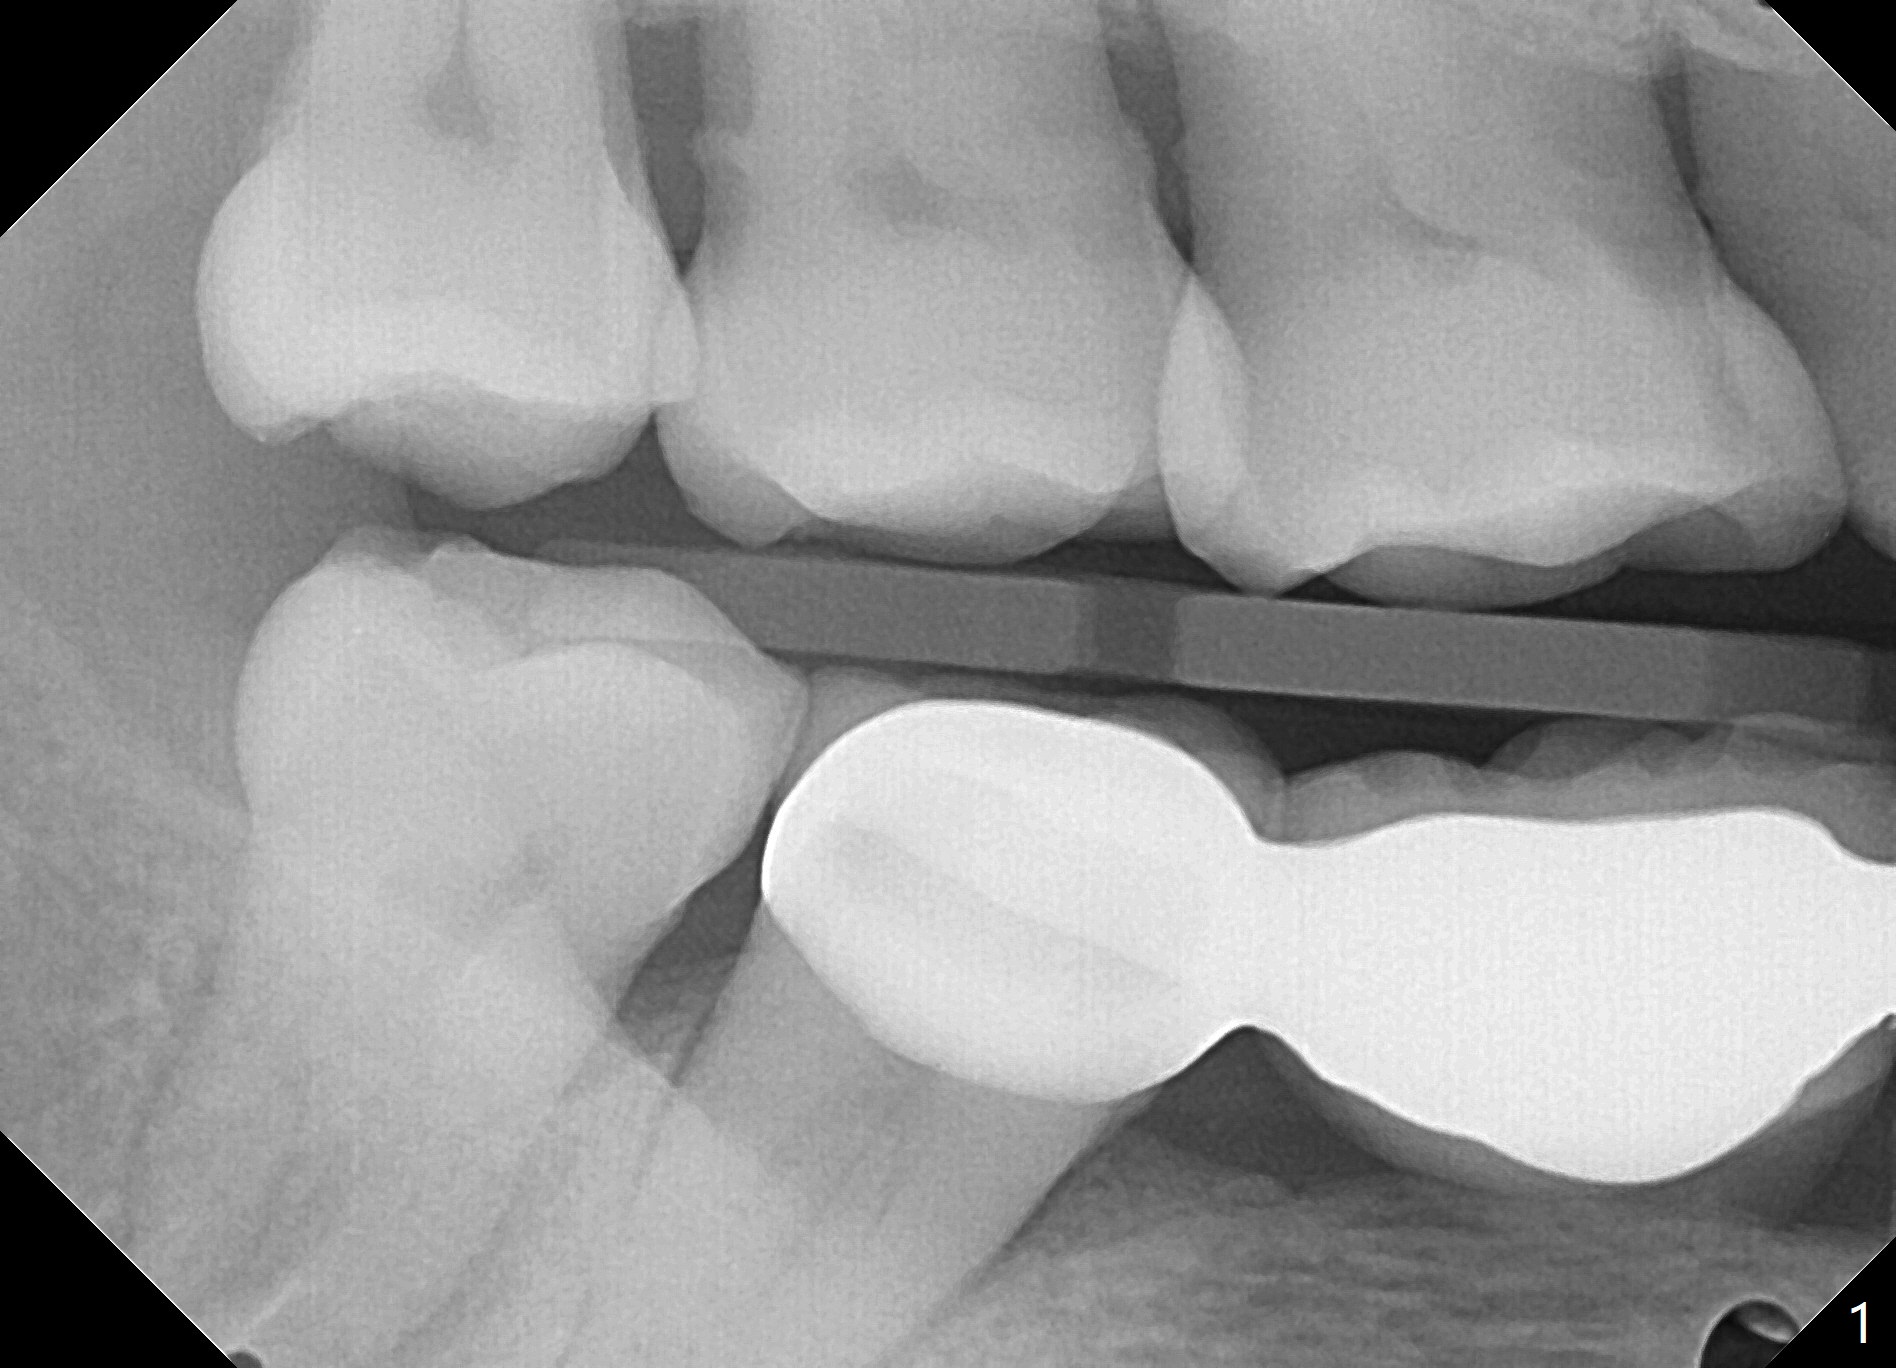

A 71 year old lady has issue with an upper bridge (#7-11, Fig.5-7). While one of the abutments (anchor teeth for FPD), #7, is "tender", the other (#11) fractures. Take Alginate impression (upper and lower) when she returns, pour models (no bubbles, 1 U, 2 L), and keep U Alginate for provisional. Section FPD at #7 and 9, take 12x9 cm CT with 2 cotton rolls and full arch impression for guide with bite registration. Prepare Endo Ice for #7 (tenderness). Tell the patient and her daughter that the lower left cantilever FPD is in bad shape, since the tooth #19 has large furca radiolucency (Fig.4 *). Next appointment should be scheduled for SRP (Fig.1-4).